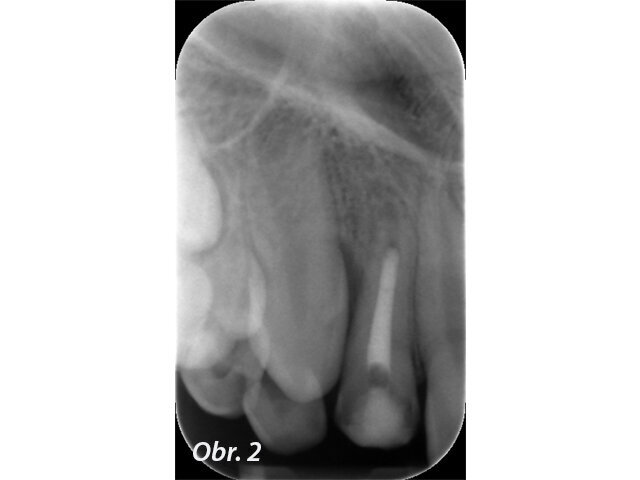

Prvním možným řešením je umístění MTA přímo do dekontaminovaného apexu zubu. U kratších rovných kořenů jde se správným instrumentáriem o poměrně snadný výkon. V případě 12letého chlapce referovaného po fraktuře zubu šlo ale o postranní řezák 12 s výrazným apikálním zahnutím, kam bylo s rigidní zahnutou koncovkou tzv. „MTA gun“ v roce 2011 nemožné aplikovat dostatečně hluboko. V dnešní době s flexibilními koncovkami MAP systému by zřejmě tento problém neexistoval. Přestože nebyl zub zcela zaplněn, předchozí dekontaminace a potentní dětská tkáň zajistily, že se veškerý zbývající prostor kořene vyplnil zřejmě dentinoidní tkání. Zub byl opatřen adhezivní dostavbou s FRC čepem a pryskyřičnou korunkou. (Obr. 1–3)